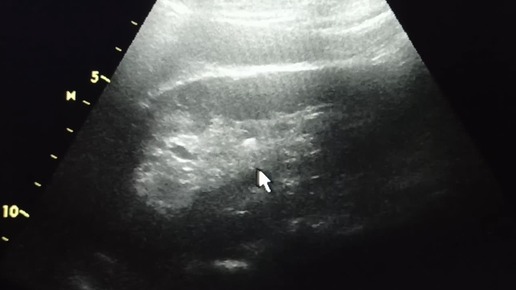

Начинающим врачам УЗИ: камни в почках